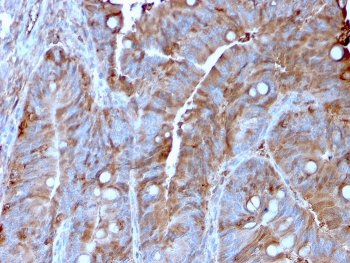

IHC staining of FFPE human colon carcinoma with MerTK antibody (clone TPKR-1). HIER: boil tissue sections in pH9 10mM Tris with 1mM EDTA for 10-20 min and allow to cool before testing.